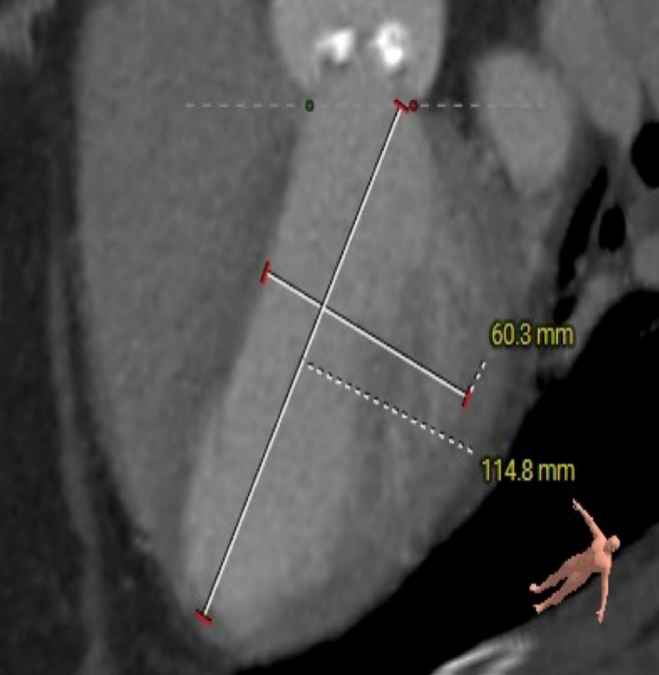

主动脉根部测量

ANNULUS

SOV DIAMETER

LVOT

STJ

瓣环水平夹角

LEFT VENTRICLE

CT数据显示该患者为三叶式主动脉瓣。

主动脉瓣瓣环周长66.2,平均周长径 21.1mm,SOV:32.2mm*36.4mm*34.1mm,瓣叶增厚,瓣上钙化分布不均,主动脉瓣环水平夹角67度,横位心。